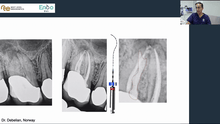

This is a full online course on primary endodontic treatment, with 8 lectures presented by Dr. Martin Trope and Gilberto Debelian.